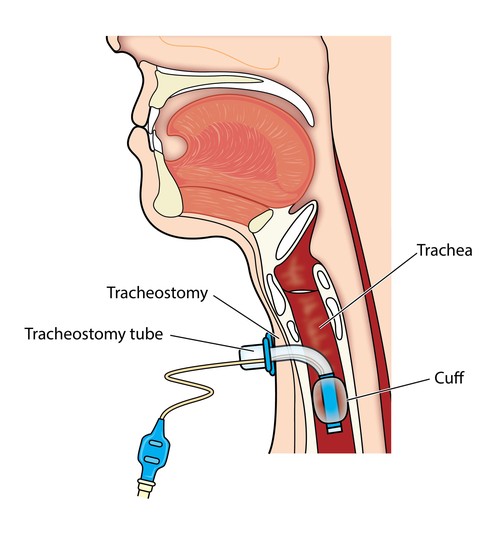

Overview

Package includes:

Days in hospital : 1 to 2 Days (For patient and one attendant)

Days in hotel : 2 Days (For patient and one attendant)

Room type in hospital : Shared

Room type in hotel : Private

Hotel category: Standard

Value added benefits of the Tracheostomy: